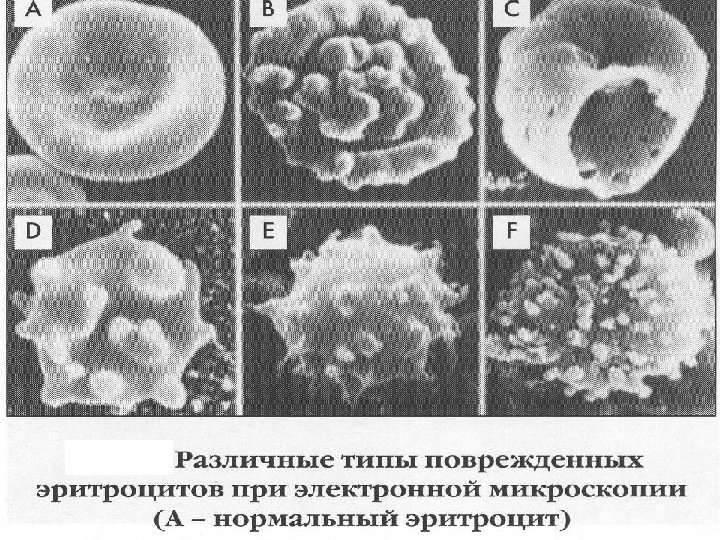

Гематурия – более 1000 эритроцитов в 1 мл мочи Гематурия как результат паренхиматозного заболевания почек § § § Продолжительная Безболезненная Микрогематурия (иногда макрогематурия) Двухсторонняя Эритроцитарные цилиндры в моче, дисморфные Эр Гематурия при заболевании мочевыводящих путей § Интермиттирующая § Связана с болью в области почек § Макрогематурия § Односторонняя § Изоморфные эритроциты